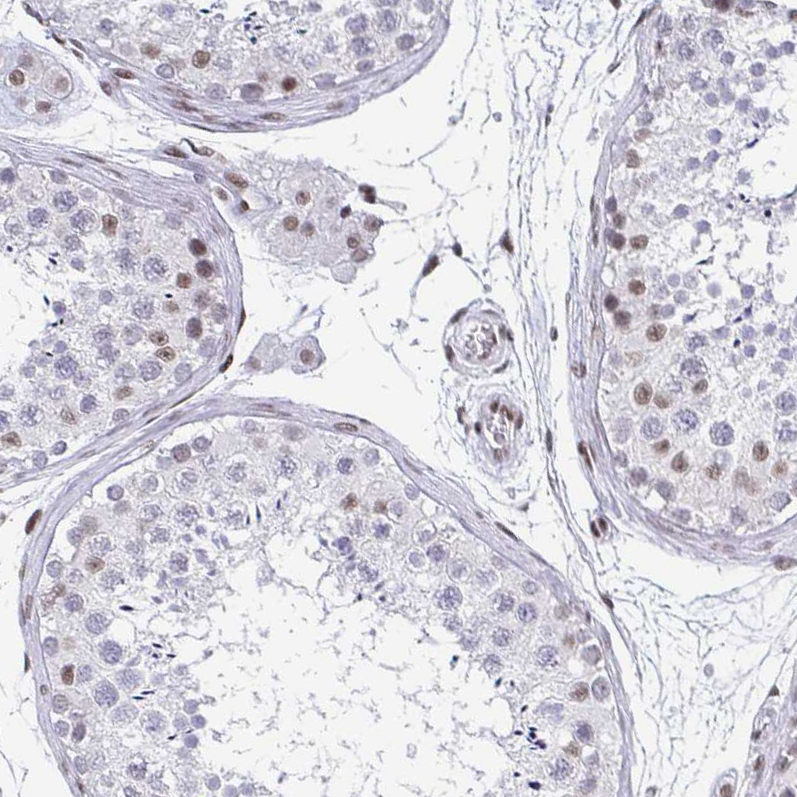

Immunohistochemical staining of human endometrium shows moderate to strong nuclear positivity in glandular and stromal cells.